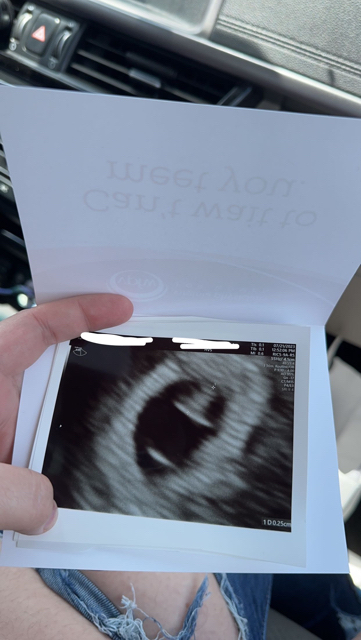

Today I went for a second opinion and while I’m having the ultrasound the doctor asked me

“They said they couldn’t see anything?” And I said nope. She responds with

“Well here’s your baby, and here’s its heart beat.”

The relief I had was so indescribable. I felt like the world was lifted from my shoulders and immediately started crying.

So far I’m only measuring 6w0d but she wants me to come back on the 31st for a dating scan seeing as I am still very early.